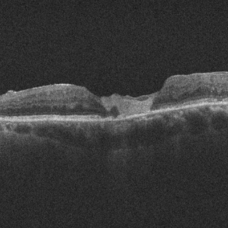

Chronic Full Thickness Macular Hole Chronic Full Thickness Macular HoleOct 25 2023 by Jessica Hampton, BS Optical-coherence tomography image of a 65-year old woman with a chronic full-thickness macular hole in the left eye, recurred following three attempts at repair with pars plana vitrectomy, membrane peel, and gas tamponade. Photographer: Dr. Diana Do, Stanford Medicine, Byers Eye Institute Condition/keywords: full thickness macular hole, optical coherence tomography (OCT)